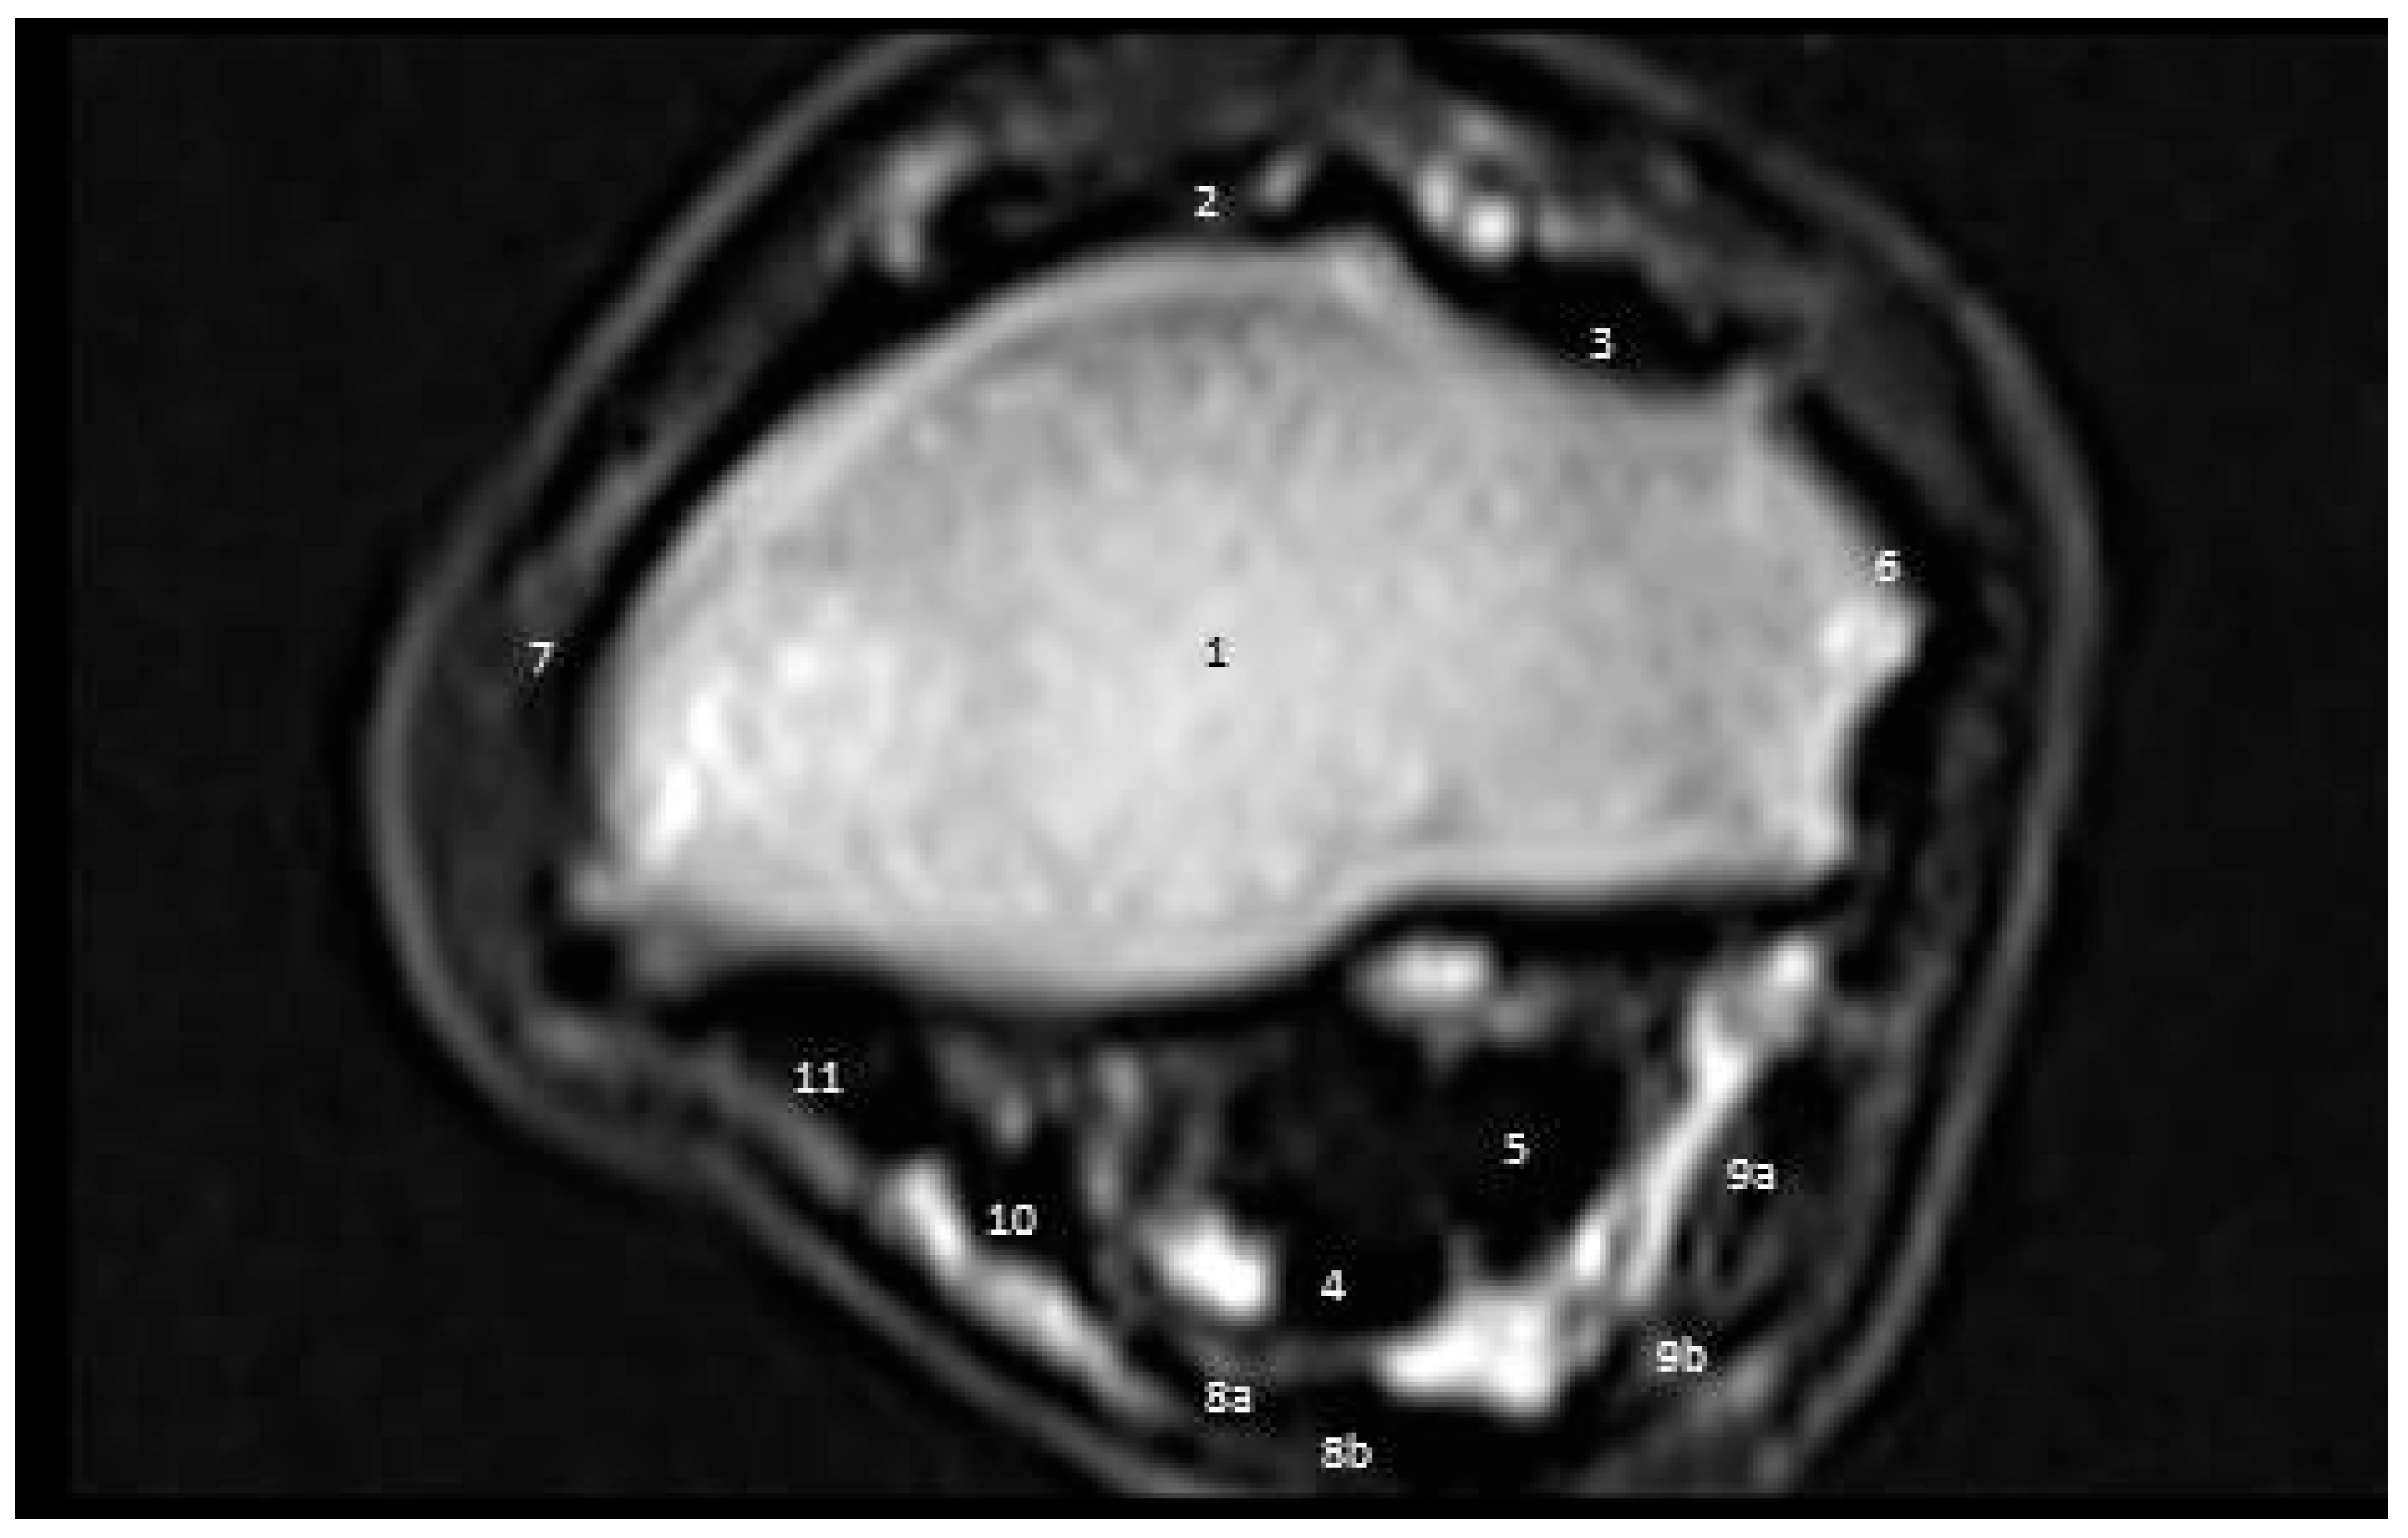

3.3.1. First Zone